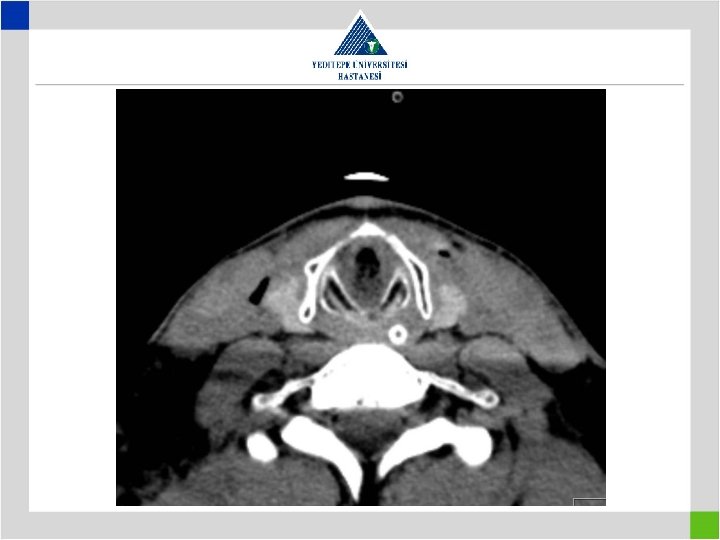

Diagnosis • Stenotic segment calculation to be correct • CT image in supine position may falsly indicate a preglottic stenosis – Overresection – increased anastomotic tension – restenosis • Pediatric trachea tolerates the tension poorly in comparison with adults – Insufficient resection – remaining fibrosis – restenosis

Iatrogenic Factors • Metal stents in bening tracheal conditions cause elongation of pathologic segment and cause the patient to loose the previously present chance of surgical cure